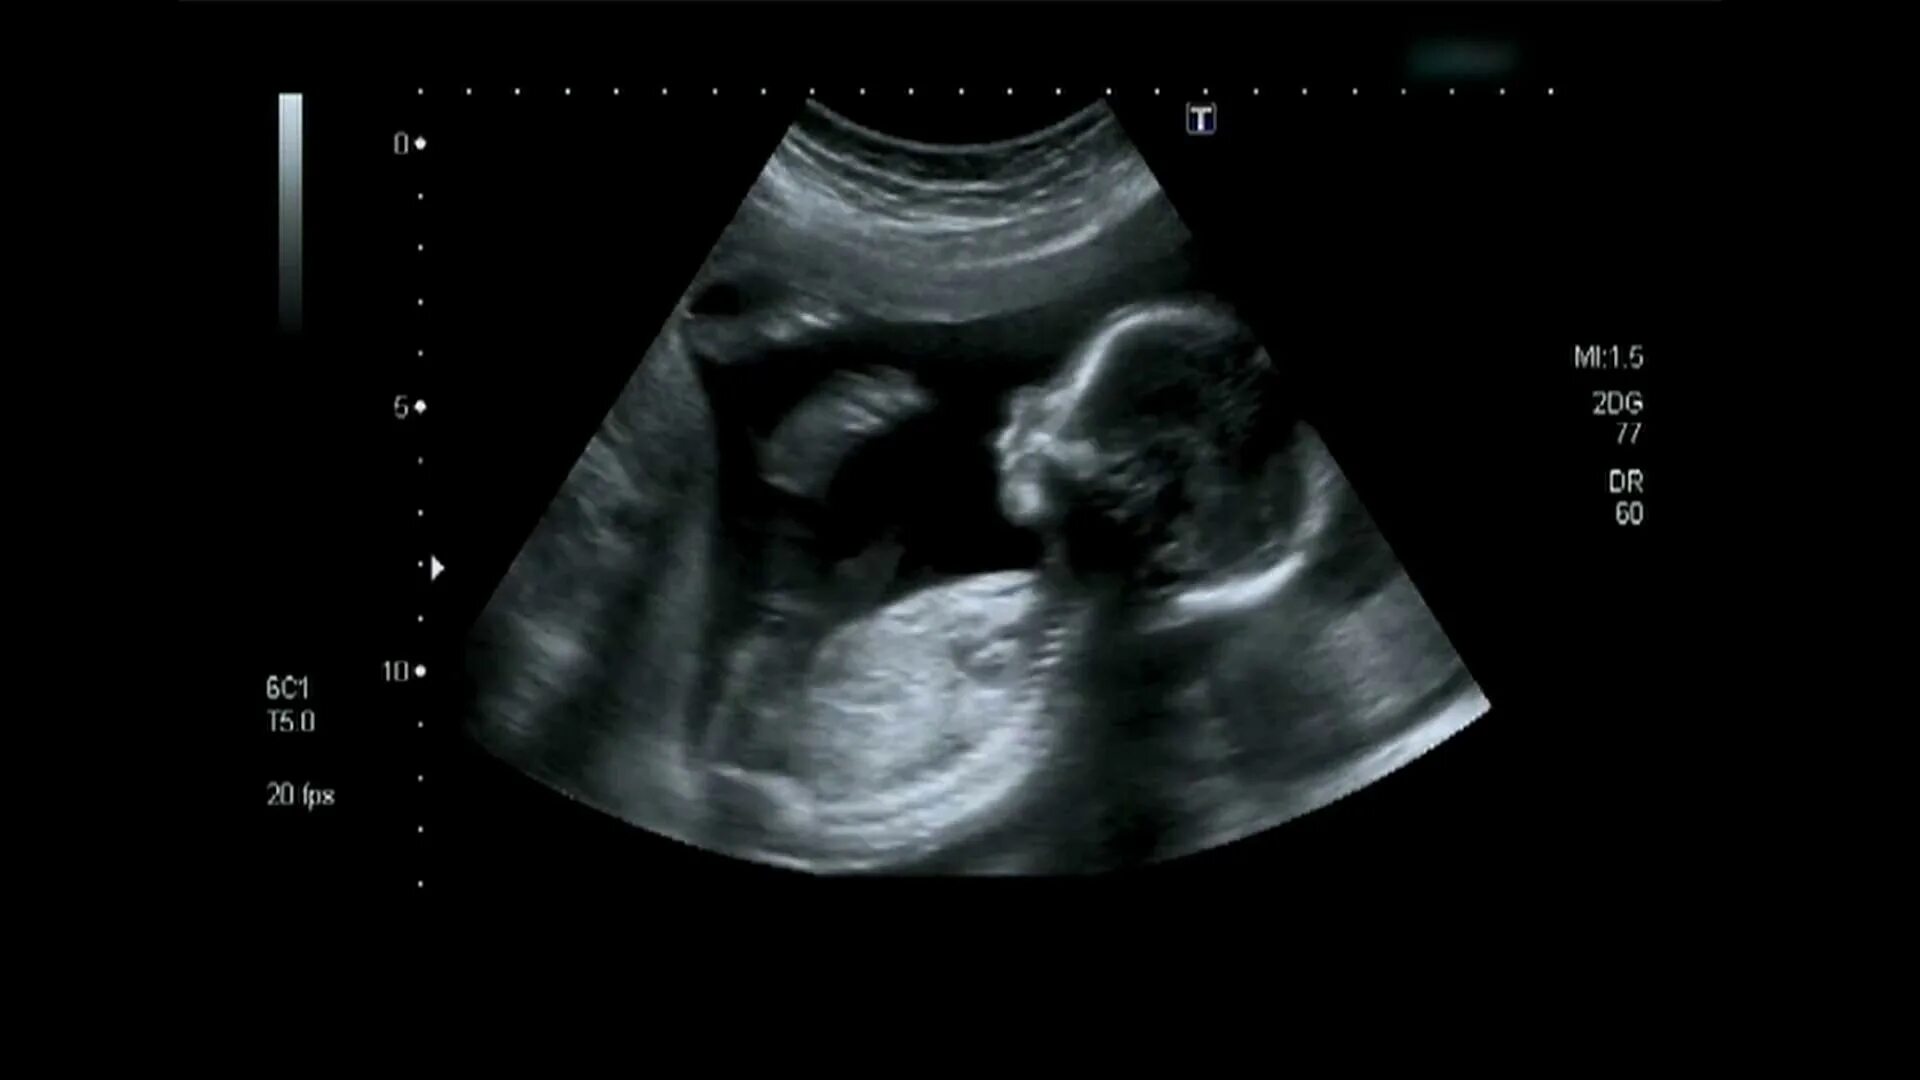

Ребенок в 20 недель беременности в животе